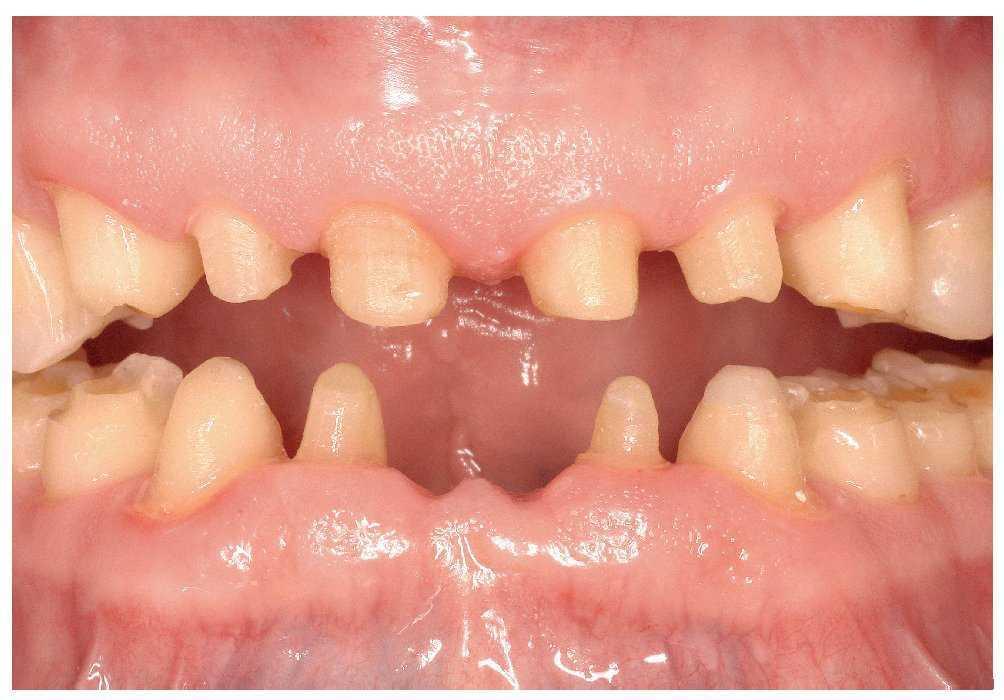

Preparación definitiva, prótesis provisional, toma de impresiones de precisión y reevaluación de la relación intermaxilar

Los dientes de los sectores anterosuperior y anteroinferior fueron preparados para recibir coronas y un puente (fig. 9). Los dientes posteroinferiores, a excepción del 48, fueron preparados para recibir coronas de recubrimiento parcial (fig. 18). Sin embargo, para asegurar las restauraciones contra la incidencia de fuerzas transversales, se tallaron cajas interproximales con un sistema de ultrasonidos (Sonicsys approx, KaVo, Biberach), eliminando con ello los puntos de contacto. A la preparación de los dientes le siguió la extracción atraumática de las piezas 31 y 41.

Figura 9. Situación a las siete semanas de la preparación y de la extracción de los dientes 31 y 41.